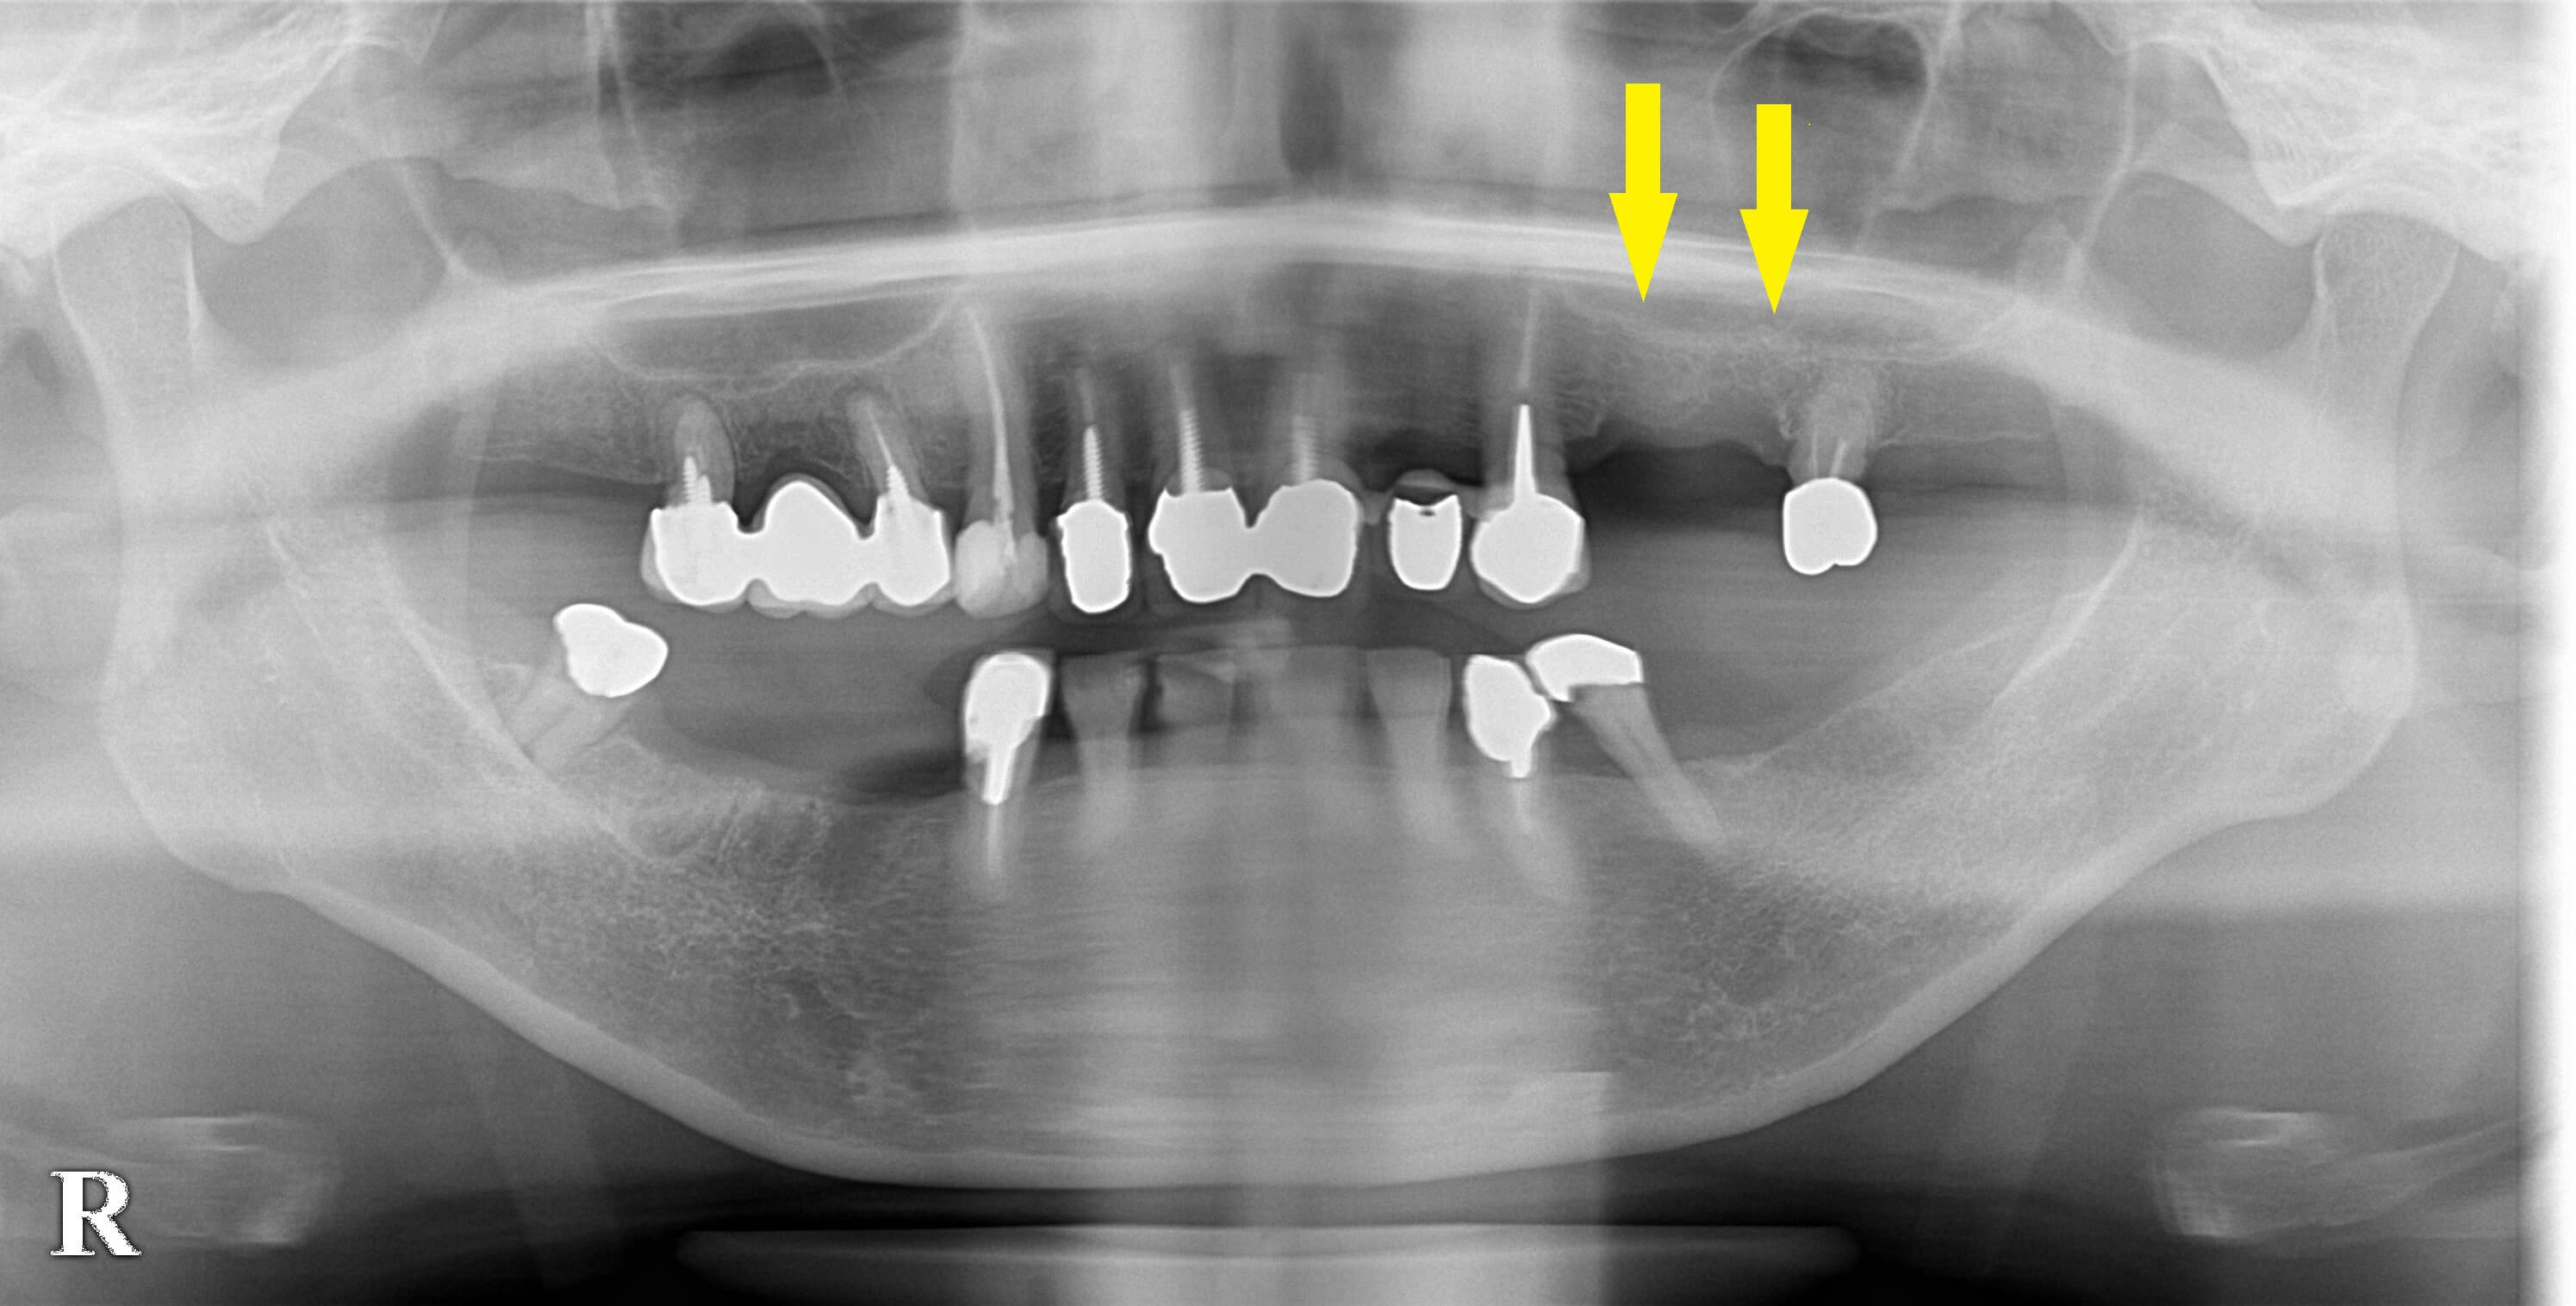

下顎の骨は問題ありませんでしたが、左側上顎の骨は高さ・幅とも不足していましたので、ソケットリフトという骨造成術で骨の高さを増し、さらに外側に人工骨を補填して、幅を拡大する骨造成術を併用することで2本のインプラント埋入を行うこととしました。

本日インプラント埋入手術、骨造成術を行いました。下の写真中段左右が手術前のCTです。

両部位ともかなりの骨量不足を認めます。

下段が手術後のCTです。

下段左の写真の部位では、人工骨がインプラントの先と、外側に補填され、インプラント体が骨で囲まれている状態にできました。